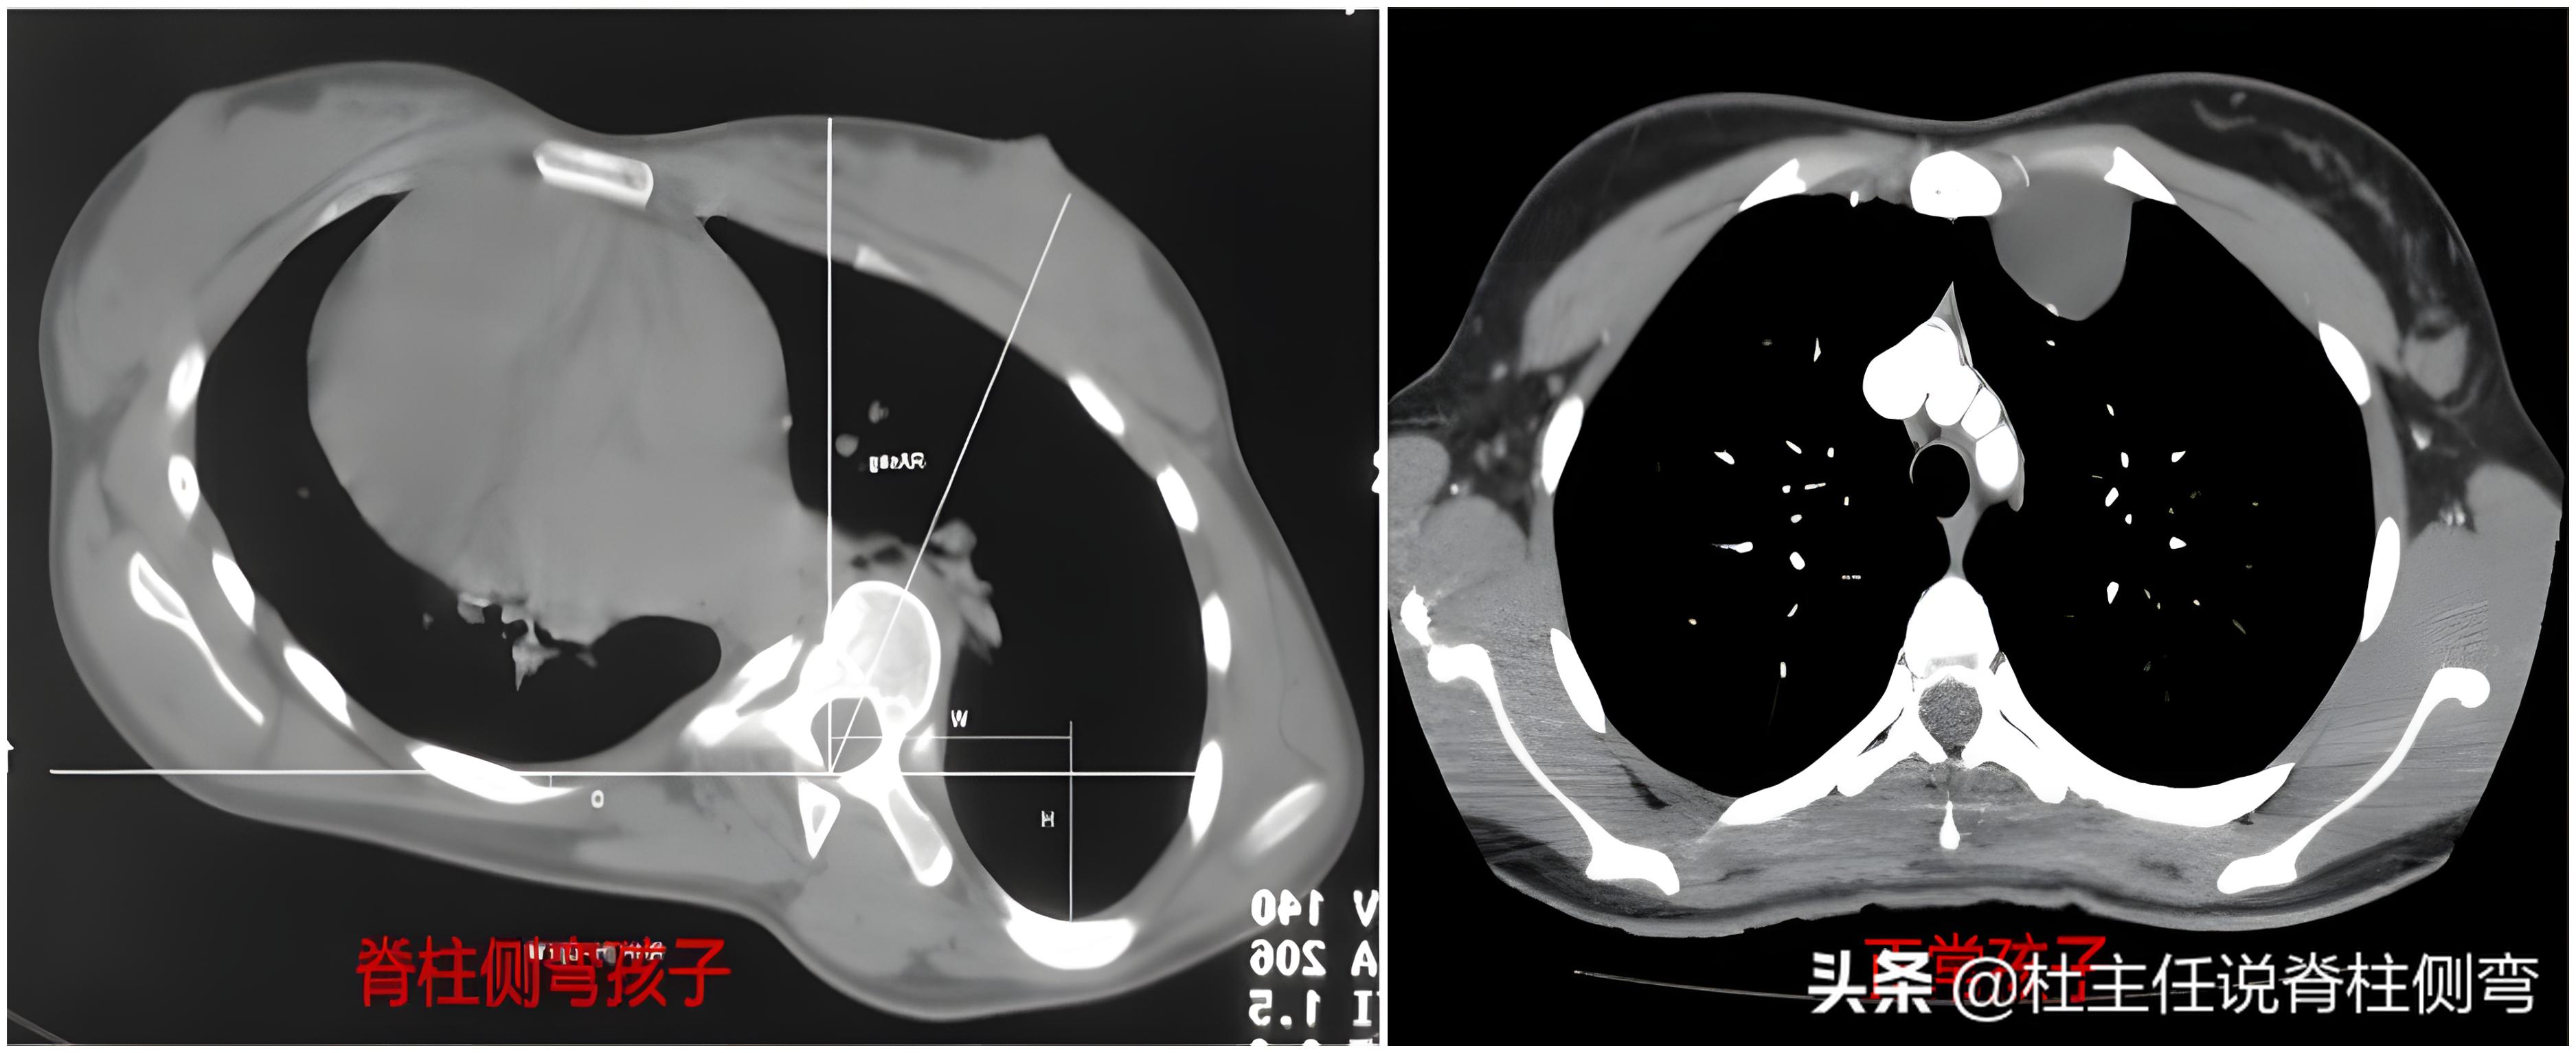

脊柱侧弯患者通常都伴有椎体的旋转,尤其是侧弯发生在胸椎段的位置,由于椎体旋转带动着我们的肋骨一起发生了转动,可能会导致 胸廓变形 ,引起肺活量降低及肺功能下降。